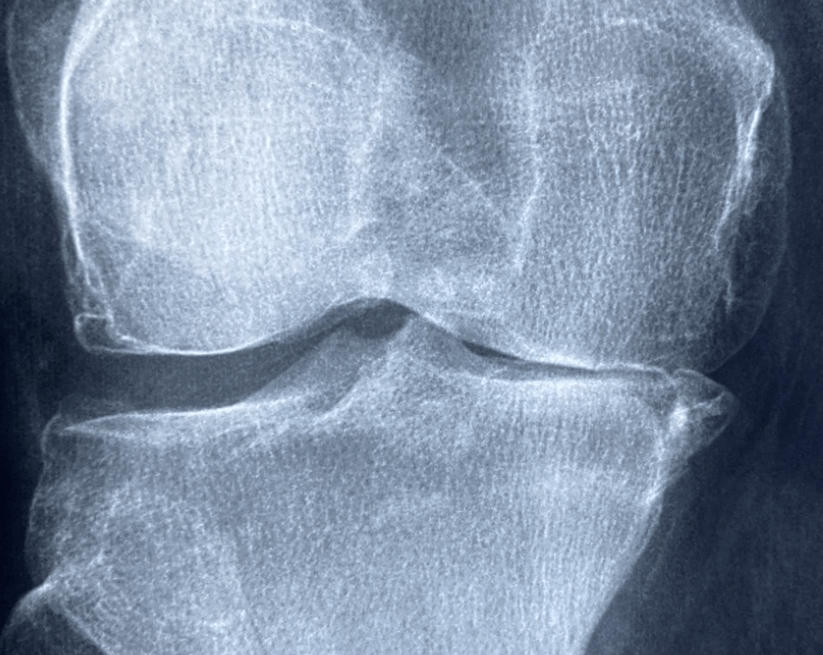

5. 수술적 치료

약물이나 운동으로도 통증이 조절되지 않는다면 관절 내시경, 인공관절 치환술과 같은 수술적 치료가 필요할 수 있습니다.

수술 후에는 재활 치료와 꾸준한 관리가 필수입니다.